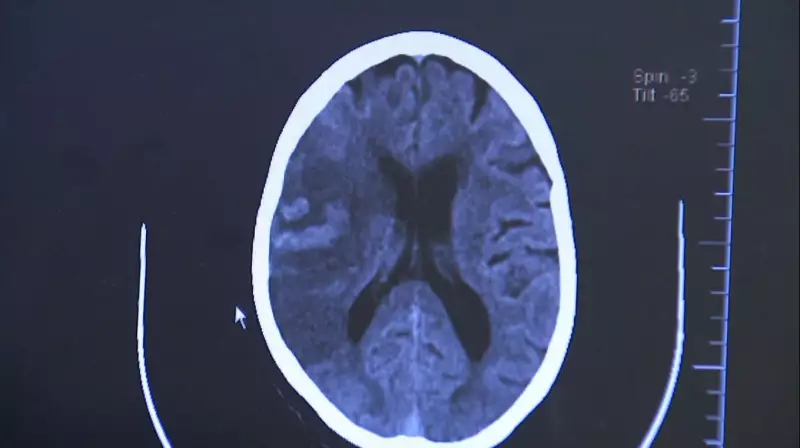

O Que é o AVC e Por Que é Tão Perigoso?

O Acidente Vascular Cerebral, popularmente conhecido como derrame, ocorre quando há interrupção do fluxo sanguíneo para o cérebro. Existem dois tipos principais:

- AVC Isquêmico: Quando um coágulo obstrui uma artéria

- AVC Hemorrágico: Quando ocorre ruptura de um vaso sanguíneo